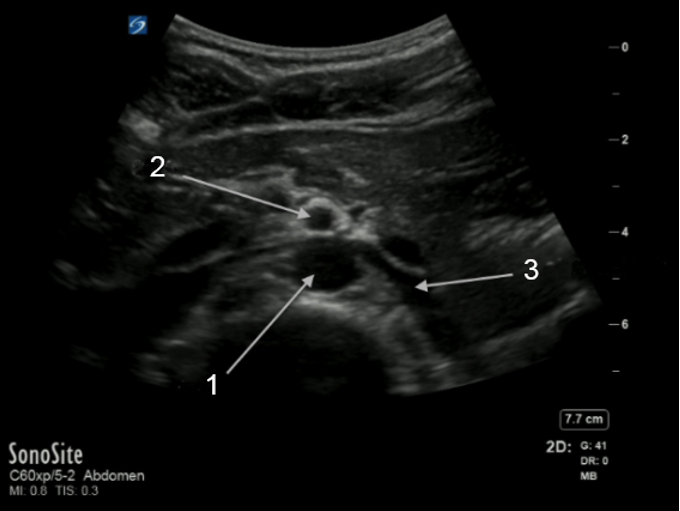

Aorta Left Renal Vein Image

Aorta

Superior Mesenteric Artery (SMA)

Left Renal Vein